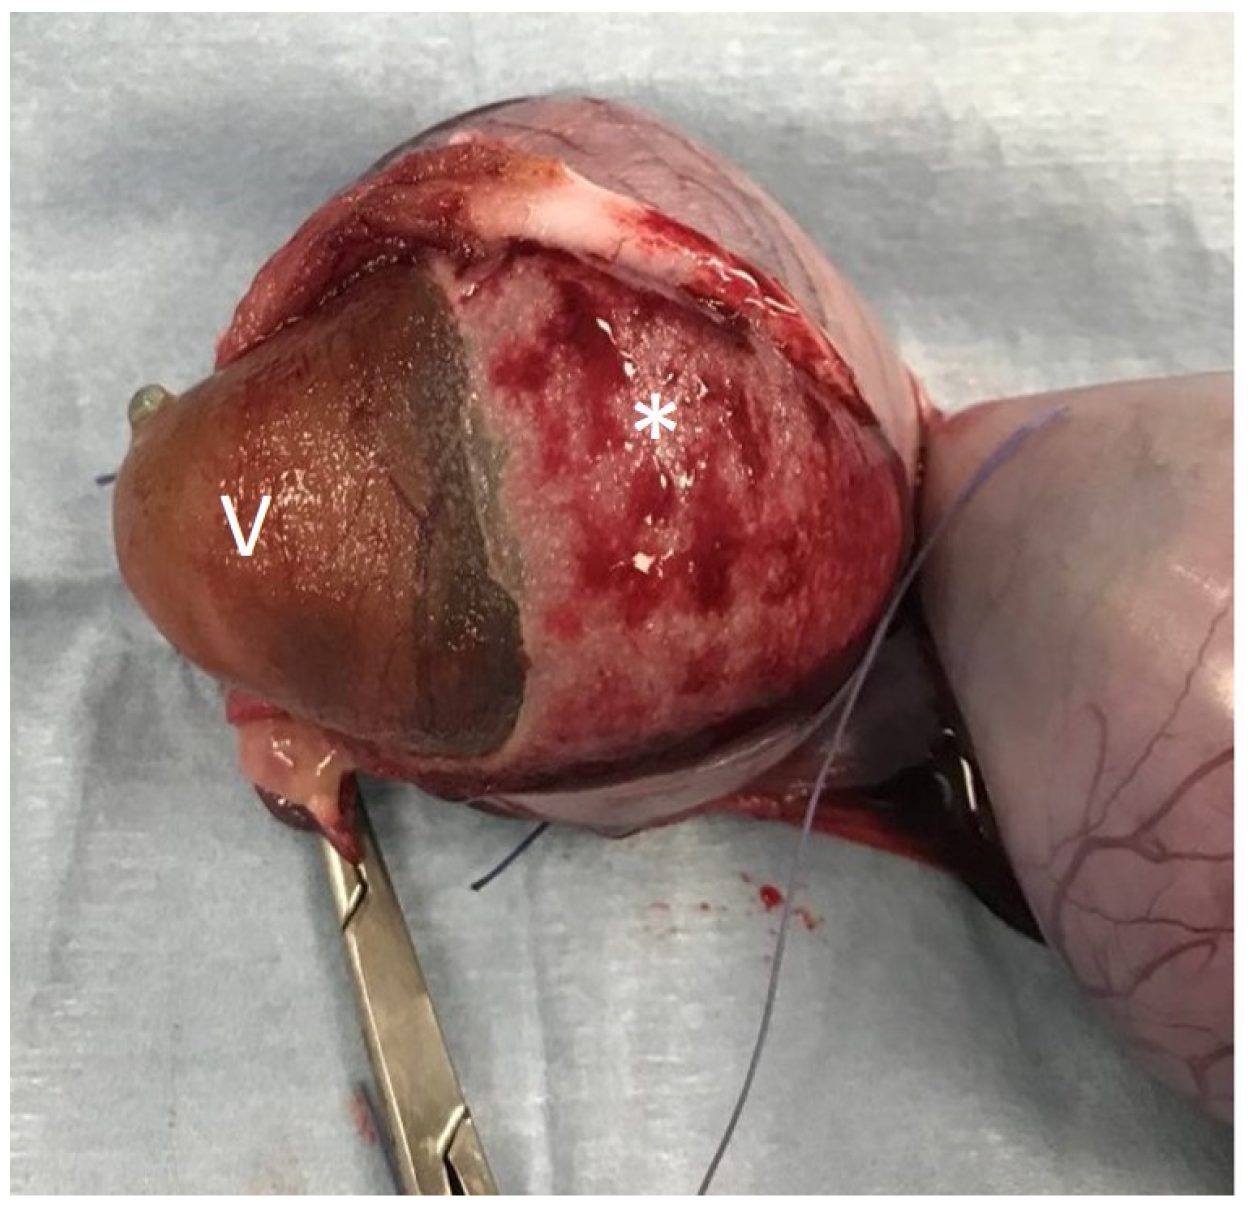

2.2. Surgical Procedure

2.3. Sample Collection